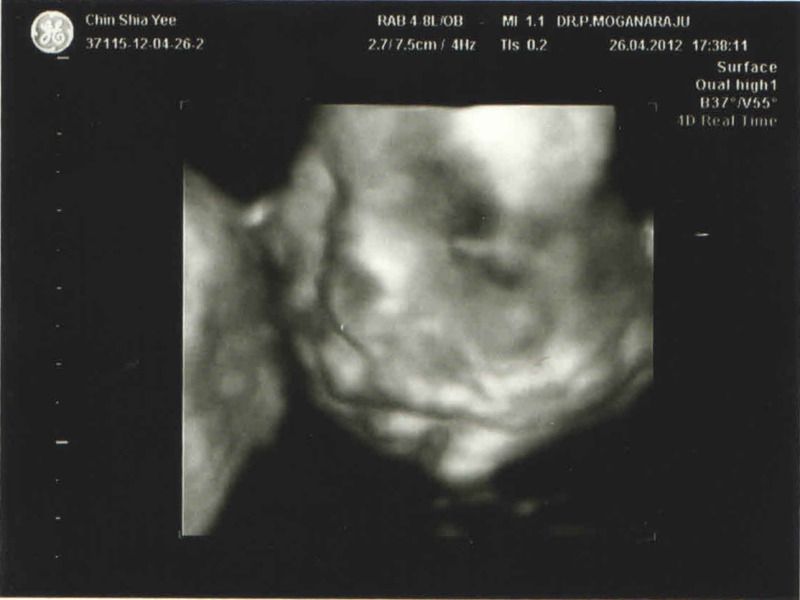

狗爸和鼠媽的龍BB Y(^_^)Y - 5/10 PG77 我回來了, 也上了產記和第一次打針喔!

雪雪,你是给Dr Moorgan看4D的吗?

想在这星期六给他做产检,可是不懂会多人吗? |